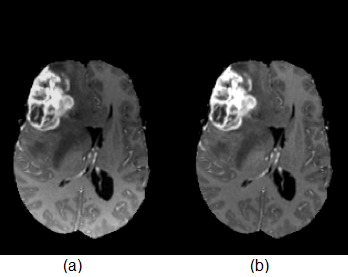

Images acquired from different MRI modalities are affected by artefacts, such as motion and field inhomogeneity [42]. These artefacts cause false intensity levels, which leads to the emergence of false positives in the predicted output. Bias field correction techniques are used to deal with artefacts in MRI. The non-parametric, non-uniform intensity normalization (N3) algorithm is a widely used method for intensity normalization and artefact removal in MR images [13]. An improved version of N3 known as N4ITK bias field correction [43] is used in this study to remove unwanted artefacts from MR images. The 3D slicer tool-kit version is used to apply bias field correction, which is an open source software that provides tools to visualize, process, and give important information regarding 3D medical images [44, 45]. The effects of intensity bias in a MR image and the result of applying bias field correction is shown in Figure 2. Higher intensity values are observed in the first scan near bottom left corner, which can lead to false positives in automated segmentation. The second scan shows better contrast near the edges by removing bias using N4ITK bias field correction.